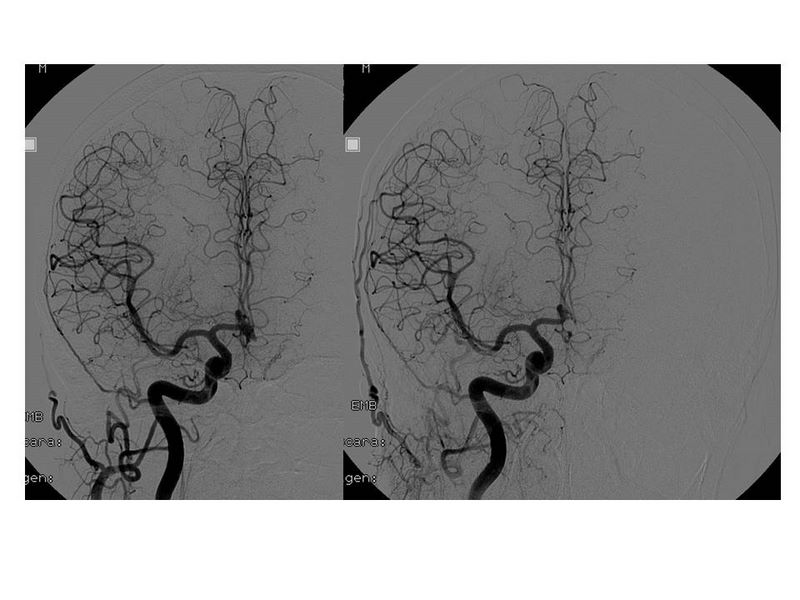

Aneurismas